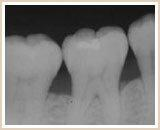

歯ぐきから血が出ていないから大丈夫と思われているかもしれませんが、歯周病は血が出ていなくても進行しています。歯周病はサイレントキラーと呼ばれるほど自覚症状がなく進行してく病気です。

その背景にも関連し、知らず知らずのうちに歯周病が進行し、日本の成人では約80%が歯周病にかかっていると言われています。

歯周病のこと~日本人の80%は歯周病です~